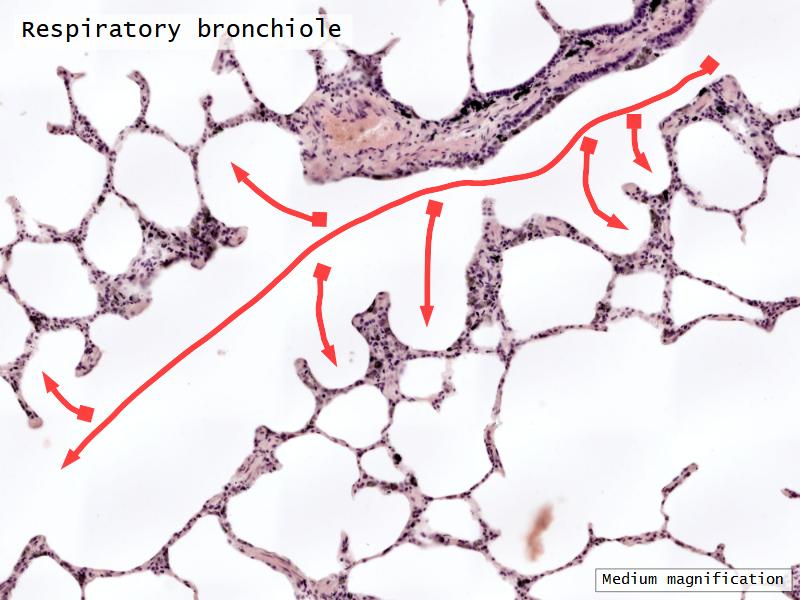

- Respiratory bronchioles

- Conducting -> Respiratory

- Simple cuboidal epithelium

- Secretory cells

- Alveoli